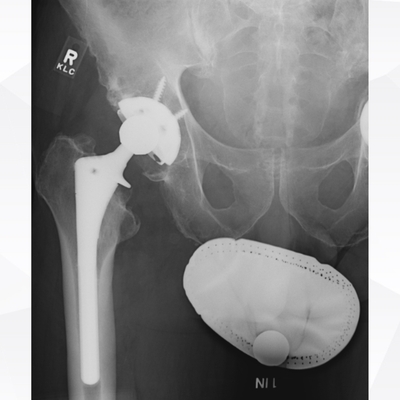

Click on an image below to view more info.